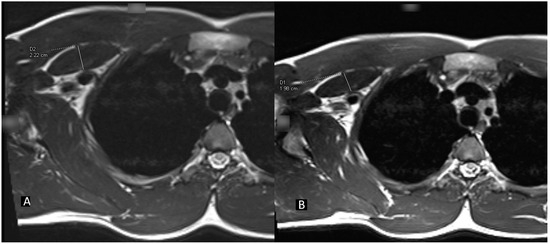

2. Case Presentation